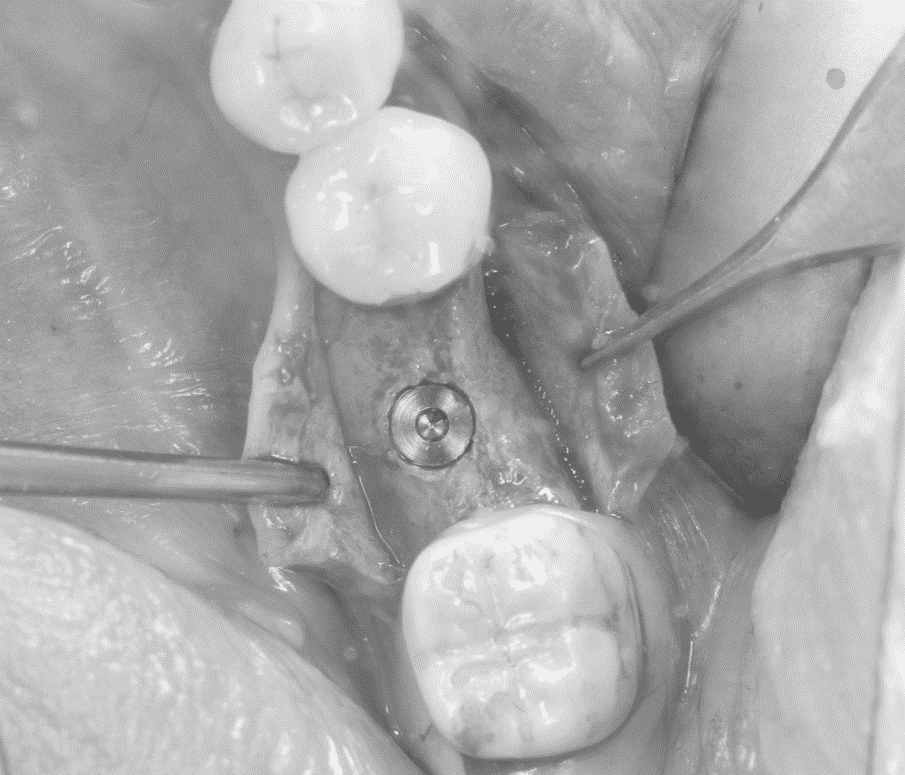

連日のオペ

こんにちは。南館歯科クリニック歯科衛生士の佐藤です。 今日は雨が降り、肌寒いですね。 さて、南館歯科クリニックでは頻繁にオペが行われています。 今回は連日のオペとなりました。 オペに向け…

事前準備

こんにちは! 南館歯科クリニックの歯科技工士兼アシスタントの鈴木です。 GWはいかが過ごされましたか? 休み明けにオペが入っているので、オペ前の最終チェックを行いました。 使用する器具の滅菌管理、足り…